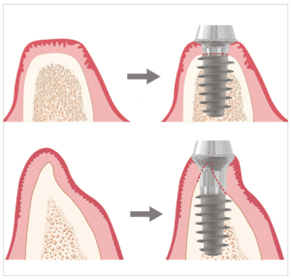

(Figure 1) Schéma de l’implant MagiCore.

MagiCore est un implant tout-en-un composé de trois parties : le Magic Fin Thread, le Magic Cuff (col) et le Magic Post (figure 1). Dans cet article, nous expliquerons les principes de développement de MagiCore dans l’ordre suivant : 1. Le Magic Cuff, 2. Le Magic Fin Thread et 3. Le Magic Post.

(Figures 2-1, 2-2) Application du Magic Cuff en fonction de la largeur de l’os.

Si les cliniciens se trouvent face à un os alvéolaire d’une largeur suffisante, comme indiqué dans la figure 2-1 (en haut), la chirurgie implantaire sera considérablement facilitée. Cependant, l’épaisseur de l’os alvéolaire varie d’un patient à l’autre, et il est fréquent de rencontrer des situations où il est difficile d’obtenir une largeur osseuse suffisante, comme illustré dans la figure 2-2 (en bas).

Dans les cas où la largeur de l’os est insuffisante, les cliniciens peuvent envisager soit de retirer l’os alvéolaire supérieur avant de poser l’implant, soit de planifier une implantation après une régénération osseuse guidée (ROG) dans la partie concave de l’os alvéolaire.

Ces deux méthodes sont réalisables, mais elles impliquent inévitablement une chirurgie invasive et des périodes de cicatrisation plus longues. Cependant, grâce à sa conception macro-innovante et à sa technique chirurgicale peu invasive, MagiCore permet de placer des implants en modifiant la forme de la gencive supérieure et en remplaçant la forme irrégulière de l’os par la section Magic Cuff, comme illustré dans la figure 2-2 (en bas).

Toutefois, pour poser des implants en utilisant cette méthode, il est important de maintenir la ligne gingivale modifiée et de veiller à ce qu’il n’y ait pas de symptômes dans la zone de contact entre le Magic Cuff et l’os alvéolaire.

(Figure 3) Placement du MagiCore dans un os de faible largeur.

Contrairement aux implants bone level, en deux parties, il n’est pas difficile de rencontrer ces conditions avec le système d’implant MagiCore (figure 3).